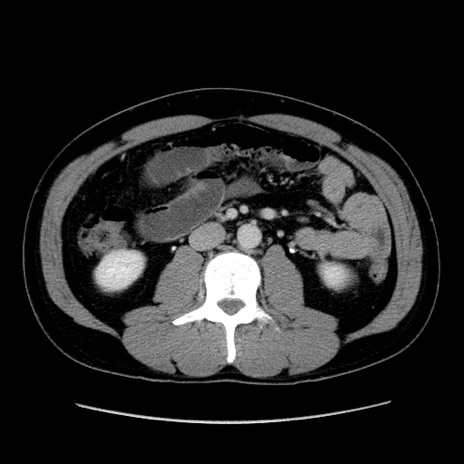

症例4(横断像)

【症例】30歳代男性

【主訴】腹痛、嘔吐

【現病歴】昨晩から突然の腹痛あり、その後嘔吐、軟便も出現。腹痛が改善しないため救急搬送となる。2日前にしめ鯖の食事歴あり。

【身体所見】意識清明、苦悶様、BP 135/90mmHg、BT 35.7℃、腹部:平坦、やや硬、心窩部〜臍部に自発痛、圧痛あり、筋性防御+、反跳痛-

【データ】WBC 8100、CRP 0.57